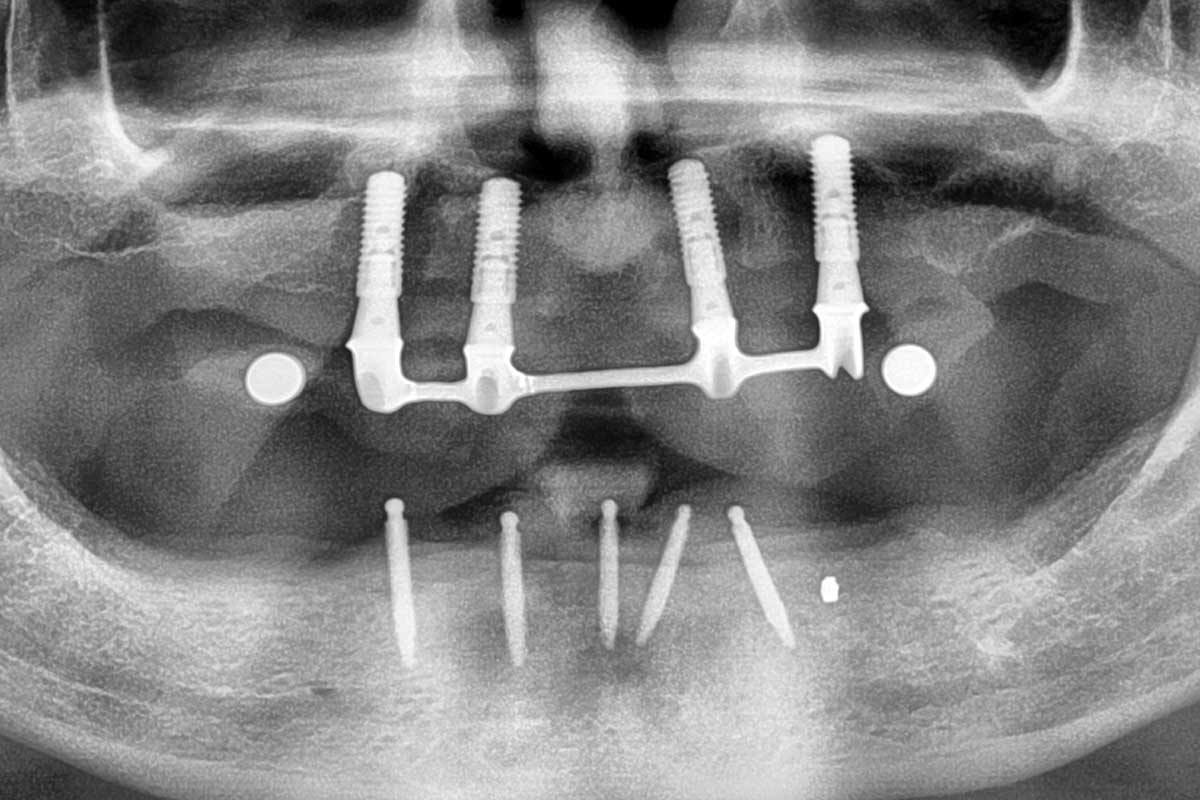

Ridge augmentation in the mandible with maxgraft® bonebuilder– Dr. R. Morger

Initial clinical situation: Free end situation in quadrant three and four

Initial x-ray showing bone loss around implants placed 5 years ago in another dental clinic